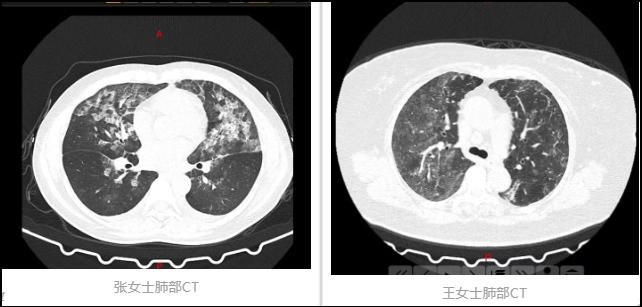

近日,郑州市中心医收治了两名患者,张女士和王女士,她们并没有发烧、咳嗽、呼吸困难等症状,不过,当看到她们的胸部CT结果,医生吓了一跳!

双肺多发毛玻璃样,正是新冠肺炎患者CT影像的典型特征。

图片来源:郑州大学附属郑州中心医院微信号

郑州市中心医院医生李凤芝介绍说:“张女士和王女士,她们两个都是以头晕乏力、闷气入院的,然后因为在疫情期间常规查胸部CT,结果显示是那种毛玻璃样改变。”

但是问题又出现了,李凤芝说,“从影像上看是非常的像(新冠肺炎),但是这个病人接触史、症状表现,然后还有包括她的血象,也是不符合的,包括她也没有去过武汉,小区也没有确诊的病例,特别纳闷这个病人到底是不是新冠。”

最后,在医生的询问下,终于找到了原因!——过敏性肺泡炎!

郑州市中心医院医生张小红在接受河南民生频道采访时说:“详细的询问病史,再问她家庭的消毒结果,病人说在家里边用84消毒,确定她就是一个过敏性肺泡炎,我问她配比,病人又不知道怎么配,看到电视上说用巴氏消毒就弄点水一混就在屋里消毒,消毒以后又不知道开窗通风,长时间地吸入高浓度的84就引起了肺部的损伤。”